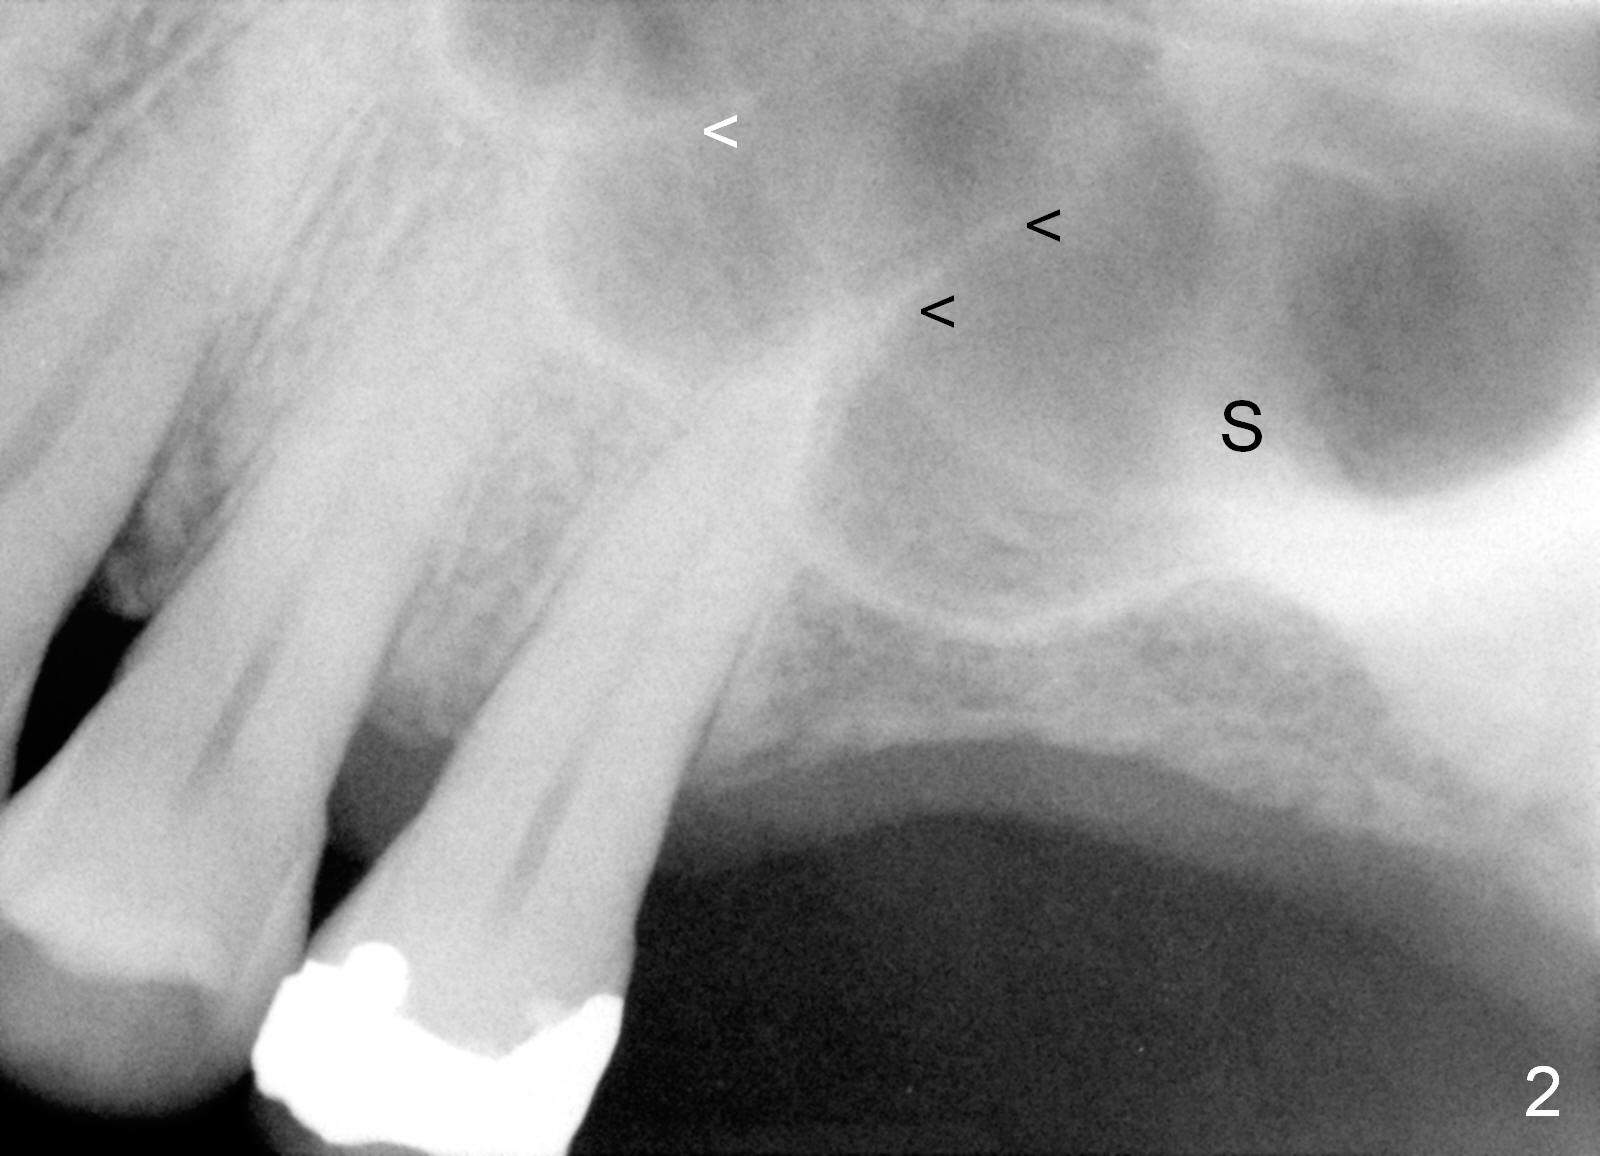

A 60-year-old man requests implant at the site of #14 (Fig.1,2, opposing a natural tooth (Fig.7)). Although bone height is limited, bone density appears high with sinus septi (S and arrowheads). The ridge seems to be wide clinically; implant will be as wide as possible. An envelop incision will be made to get the best visibility (as compared to tissue punch). At entry point, the bone height is 2.5 mm (Fig.3 red line); as the implant or osteotomy diameter increases, bone contact enhances (pink lines). If lateral window approach is adopted, a longer implant will be chosen (14 mm in Fig.3 vs. 11 mm in Fig.4, both tissue-level). The stronger distal septum may deviate the apical portion of the longer implant (Fig.3 arrow).